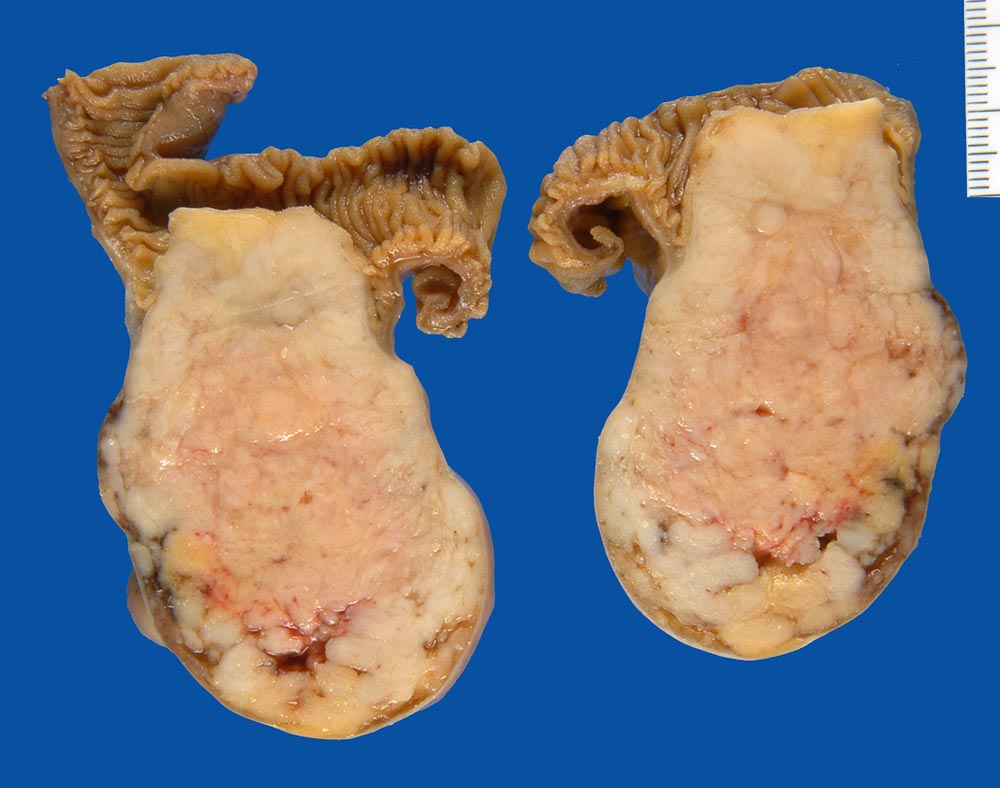

Makroskopisch imponieren kleine Tumoren als peritoneale, intramurale oder submuköse Knoten. Grössere Tumoren wölben sich oft vor und können ulzerieren. Die Schnittfläche ist weisslich und kann Einblutungen, Zysten, Fibroseareale oder Nekrosen aufweisen. Histologisch werden Spindelzelltyp (70%), Epitheloidzelltyp (20%) oder gemischtzelliger Typ (10%) unterschieden. Der histologische Subtyp scheint keinen Zusammenhang mit zugrundeliegender Mutation, Therapieansprechen und Prognose zu haben. Gelegentlich sind vor allem die kleineren Tumoren zellarm und kollagenreich.

• Scharf begrenzter kugeliger Tumor in der Submukosa des Magenantrums

• Risikostratifikation nach Miettinen und Lasota (2006): Very low risk (sehr niedriges Risiko für Metastasen oder tumorbedingte Mortalität): Lokalisation im Magen, Grösse 22mm, fehlende Mitosen.